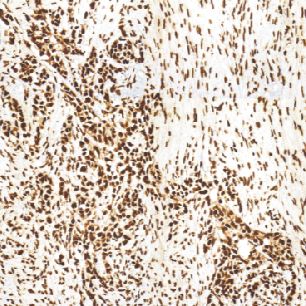

CDK4兔抗人CDK4单克隆抗体

细胞周期蛋白依赖性激酶4(CDK4)是丝氨酸/苏氨酸蛋白激酶家族的成员之一,它是蛋白激酶复合体的催化亚基,对细胞周期G1期的发展起着重要的作用。据报道,在许多肿瘤中,都可以检测到CDK4的过表达,如口腔鳞状细胞癌、胰腺癌(内分泌肿瘤)、肺癌、乳腺癌和结肠癌。CDK4的表达与肿瘤的发展有关。

- 阳性部位:胞核

- 适用组织:石蜡切片

- 预处理:热修复